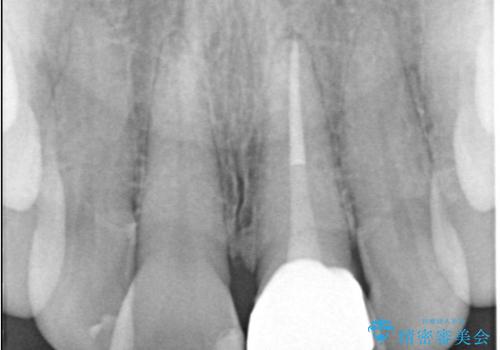

- 以前の根管治療後に生じた左上1番の前歯の変色を気にされて来院されました。患者様のご希望を伺い、オールセラミッククラウンによる審美修復を提案。既根管治療歯であるため、土台の状態や周囲の歯の色調を詳細に分析し、患者様の顔貌に調和した自然で美しい口元を実現するための治療計画を立てました。

治療では、変色した歯を形成した後、精密なシリコン印象材で型取りを行いました。この型取りから、患者様の歯の色や形、透明感を忠実に再現したオーダーメイドのオールセラミッククラウンを作製。金属を一切使わないため、アレルギーの心配がなく、歯ぐきの変色も防ぎます。技工士と連携し、天然歯と見分けがつかないほどの自然な仕上がりを追求。機能性と審美性を兼ね備えた、理想的な前歯を取り戻していただけました。